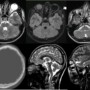

Axial T2 weighted image(a) show faint cystic changes showing FLAIR inversion(b) within the cerebellar parenchyma(blue arrow), pontine hypoplasia with a midline pontine cleft with absence of bulging contour of the facial colliculus(white arrow). Additionally phthisis bulbi of right eye observed(yellow arrow)

Axial T2 weighted sections at the level of medulla(c) show butterfly appearance of medulla oblongata

Axial sections of bone window(d) show undulating contour of the inner table of skull.

Sagittal T2(e) weighted sections at the level of massa intermedia show the profound brainstem hypoplasia.

Parasagittal T2 (f)weighted sections at the level of temporal pole demonstrate polymicrogyric contour of the frontal cortical grey matter.